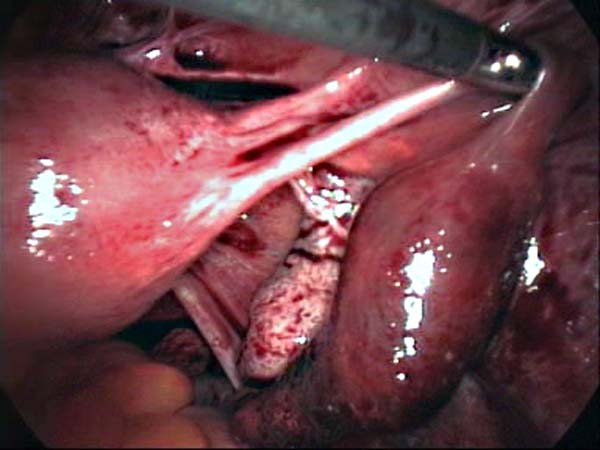

Photos laparoscopie Kyste ovarien Cystectomie ovarienne Septum utérin Grossesse tubaire